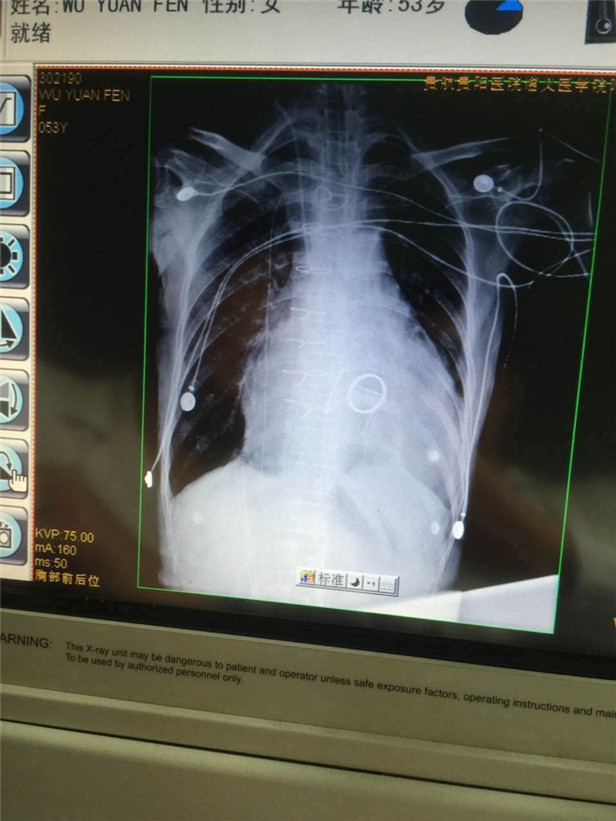

(术后心脏的照片)

事后,在徐平教授近5小时的努力下,患者吴女士异常增大的心脏缩小了1/2,成功完成了“瘦身”。术后,吴女士各种不适症状消失,心功能逐渐改善,目前已能够下床活动。